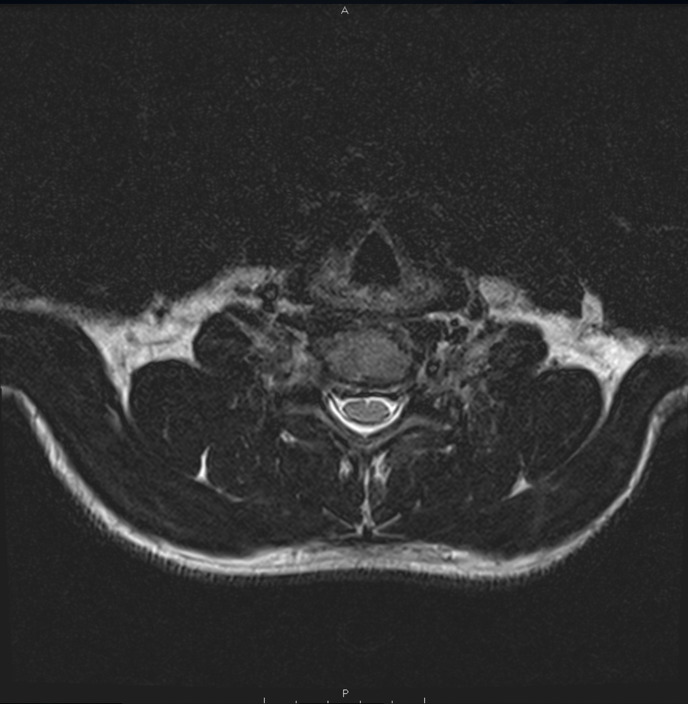

Case description: A 37-year-old male and Brazilian Jiu Jitsu athlete with cervical radiculopathy underwent a C5-C6 and C6-C7 discectomy with CTDR. The subject attended PT for 14 sessions across 16 weeks. Interventions included manual therapy (soft tissue and joint mobilization), therapeutic exercise targeting cervical spine, thoracic spine and upper extremity mobility and strength, and weightlifting body mechanics education. Radiographic confirmation of prosthesis placement and healing was monitored at postoperative weeks six and 12. The PT program was designed and progressed according to tissue healing timelines, subject response, clinical reasoning, and sport-specific demands.